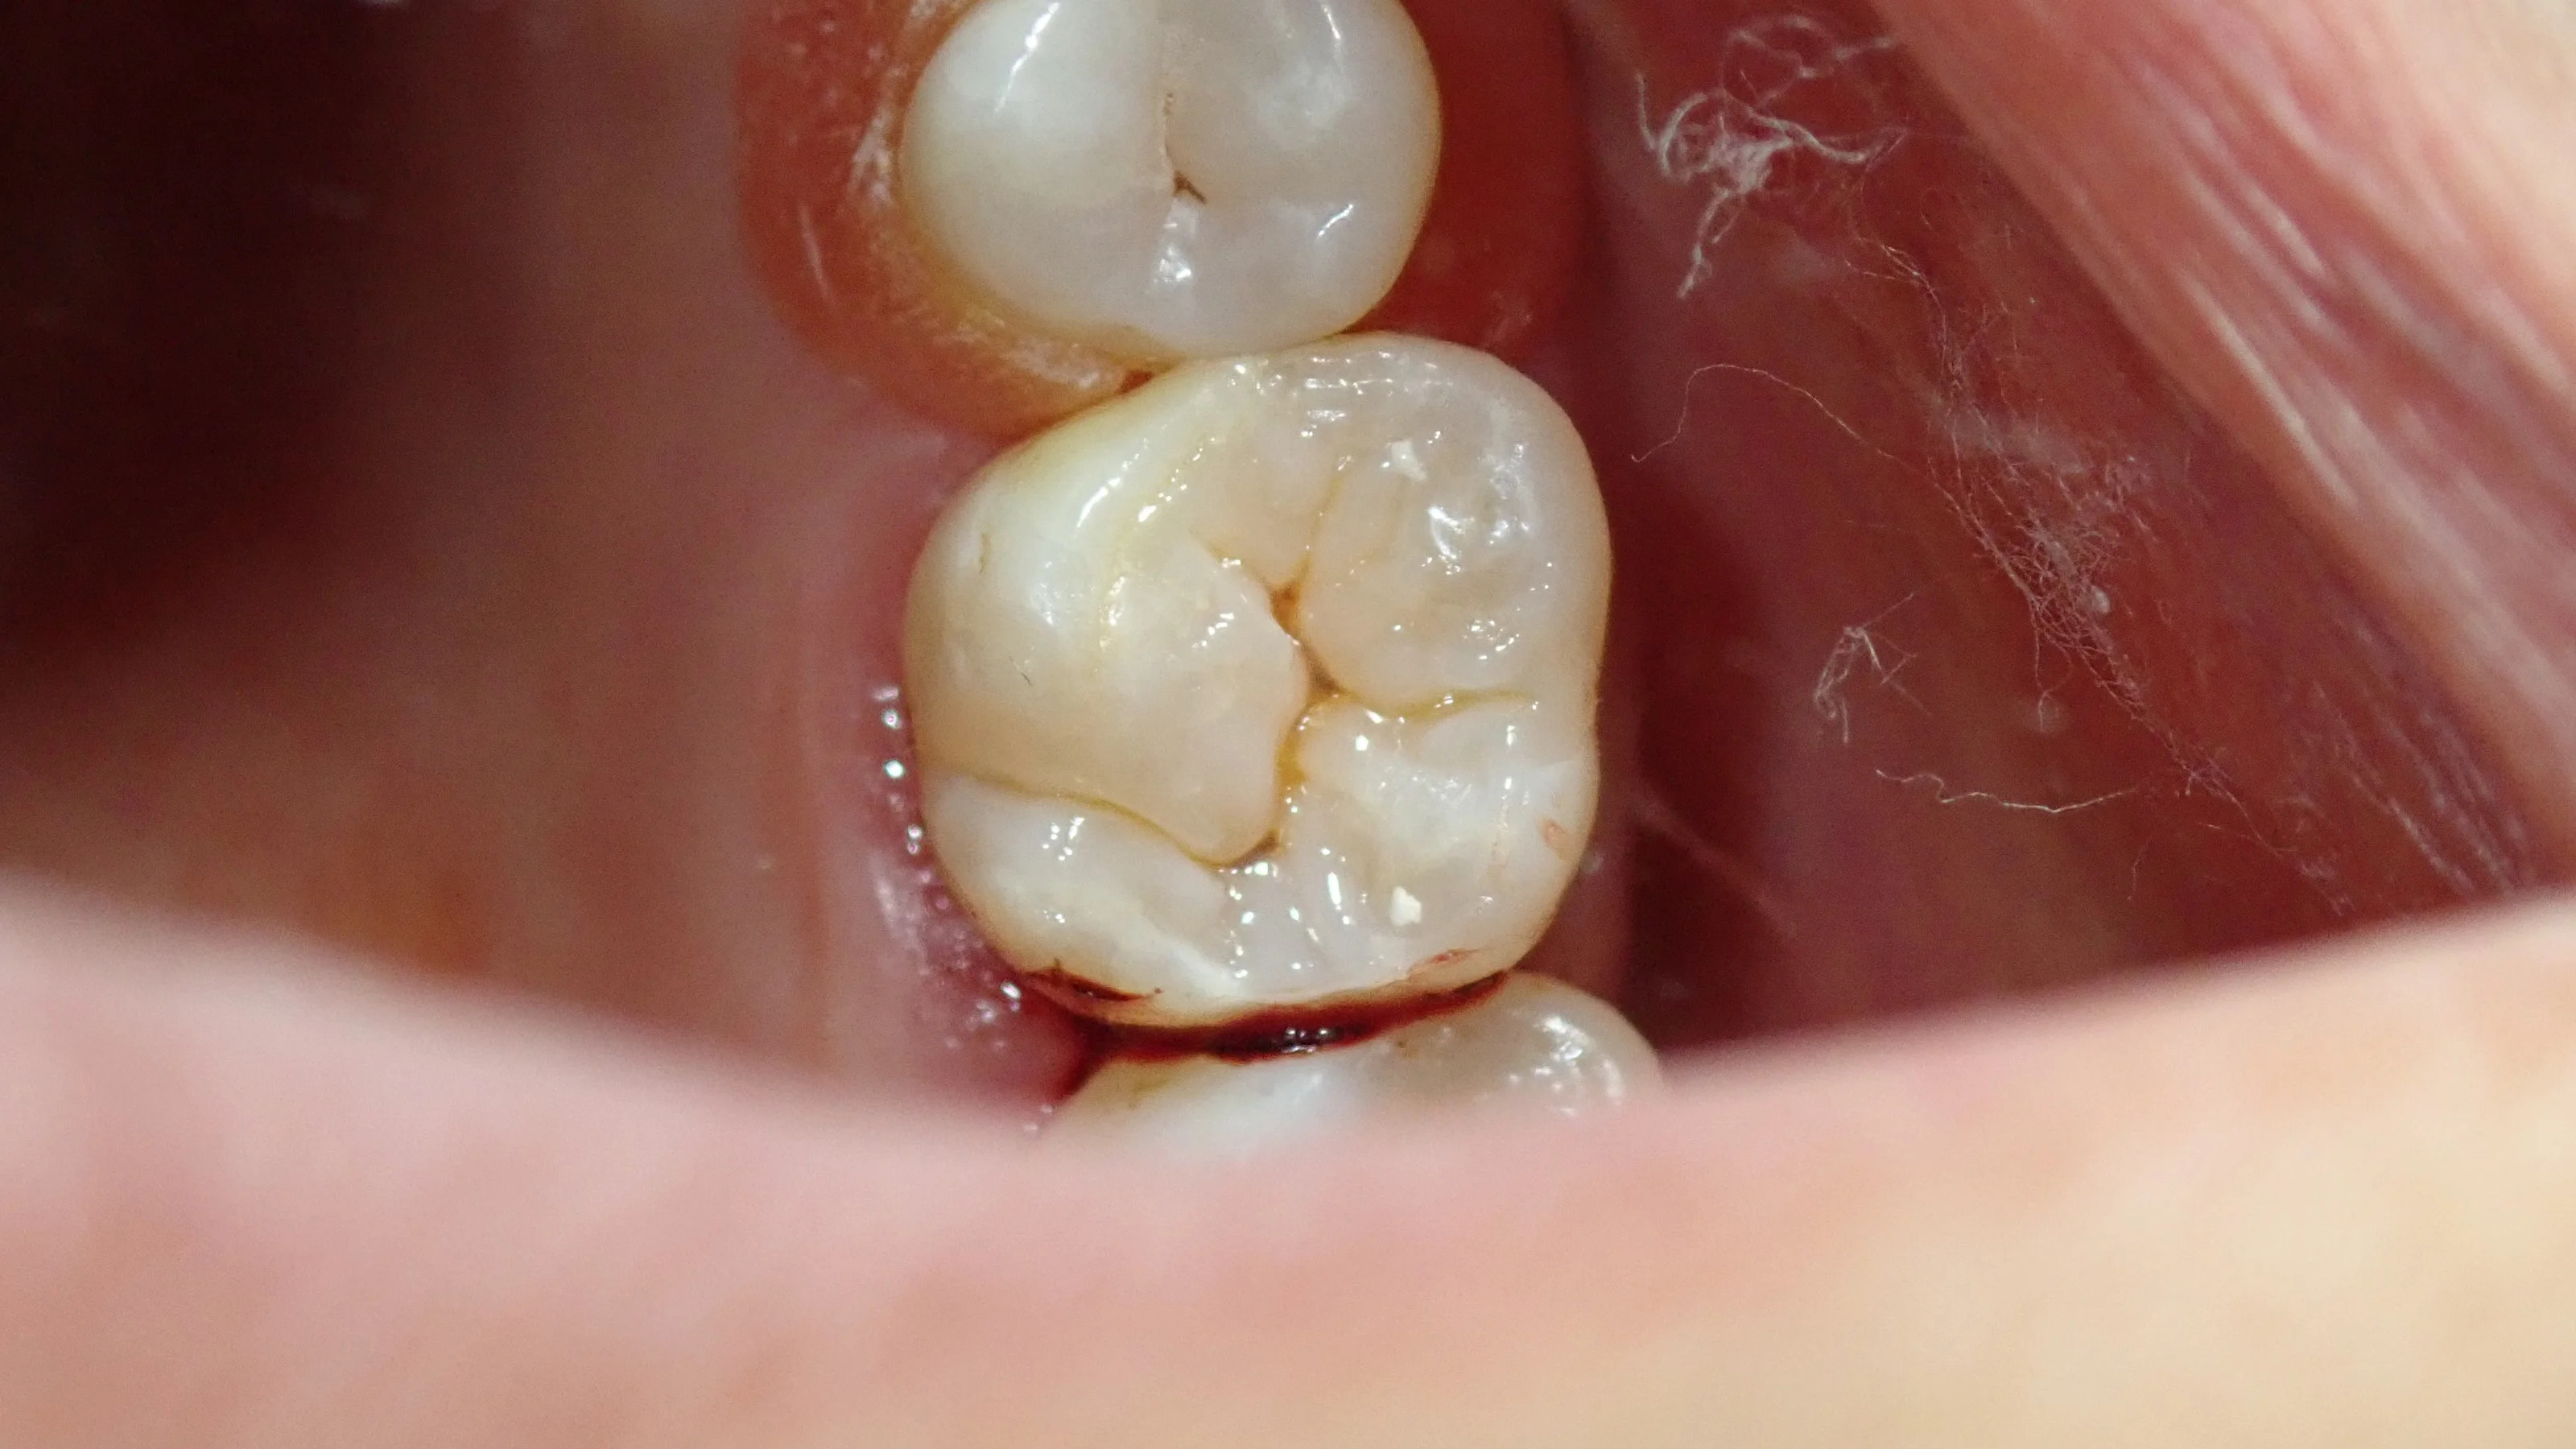

と、いう訳で、噛み合わせの治療後、研磨まで終わった画像がこちらです。

歯を強固に乾燥させていたため、最初に比べると若干色合いが変わってしまっています。

その為、詰めたところが少し浮いているように感じられるかもしれませんが、再度水分を吸ったら1週間くらいで色は馴染んできます。

歯の溝の部分の色を再現することを「ステイニング」と言いますが、これを行うと歯に立体感が出て、より自然な歯に仕上がります。

フロスでも引っかかるところは皆無ですので、十分に長持ちさせることが出来ると思います。